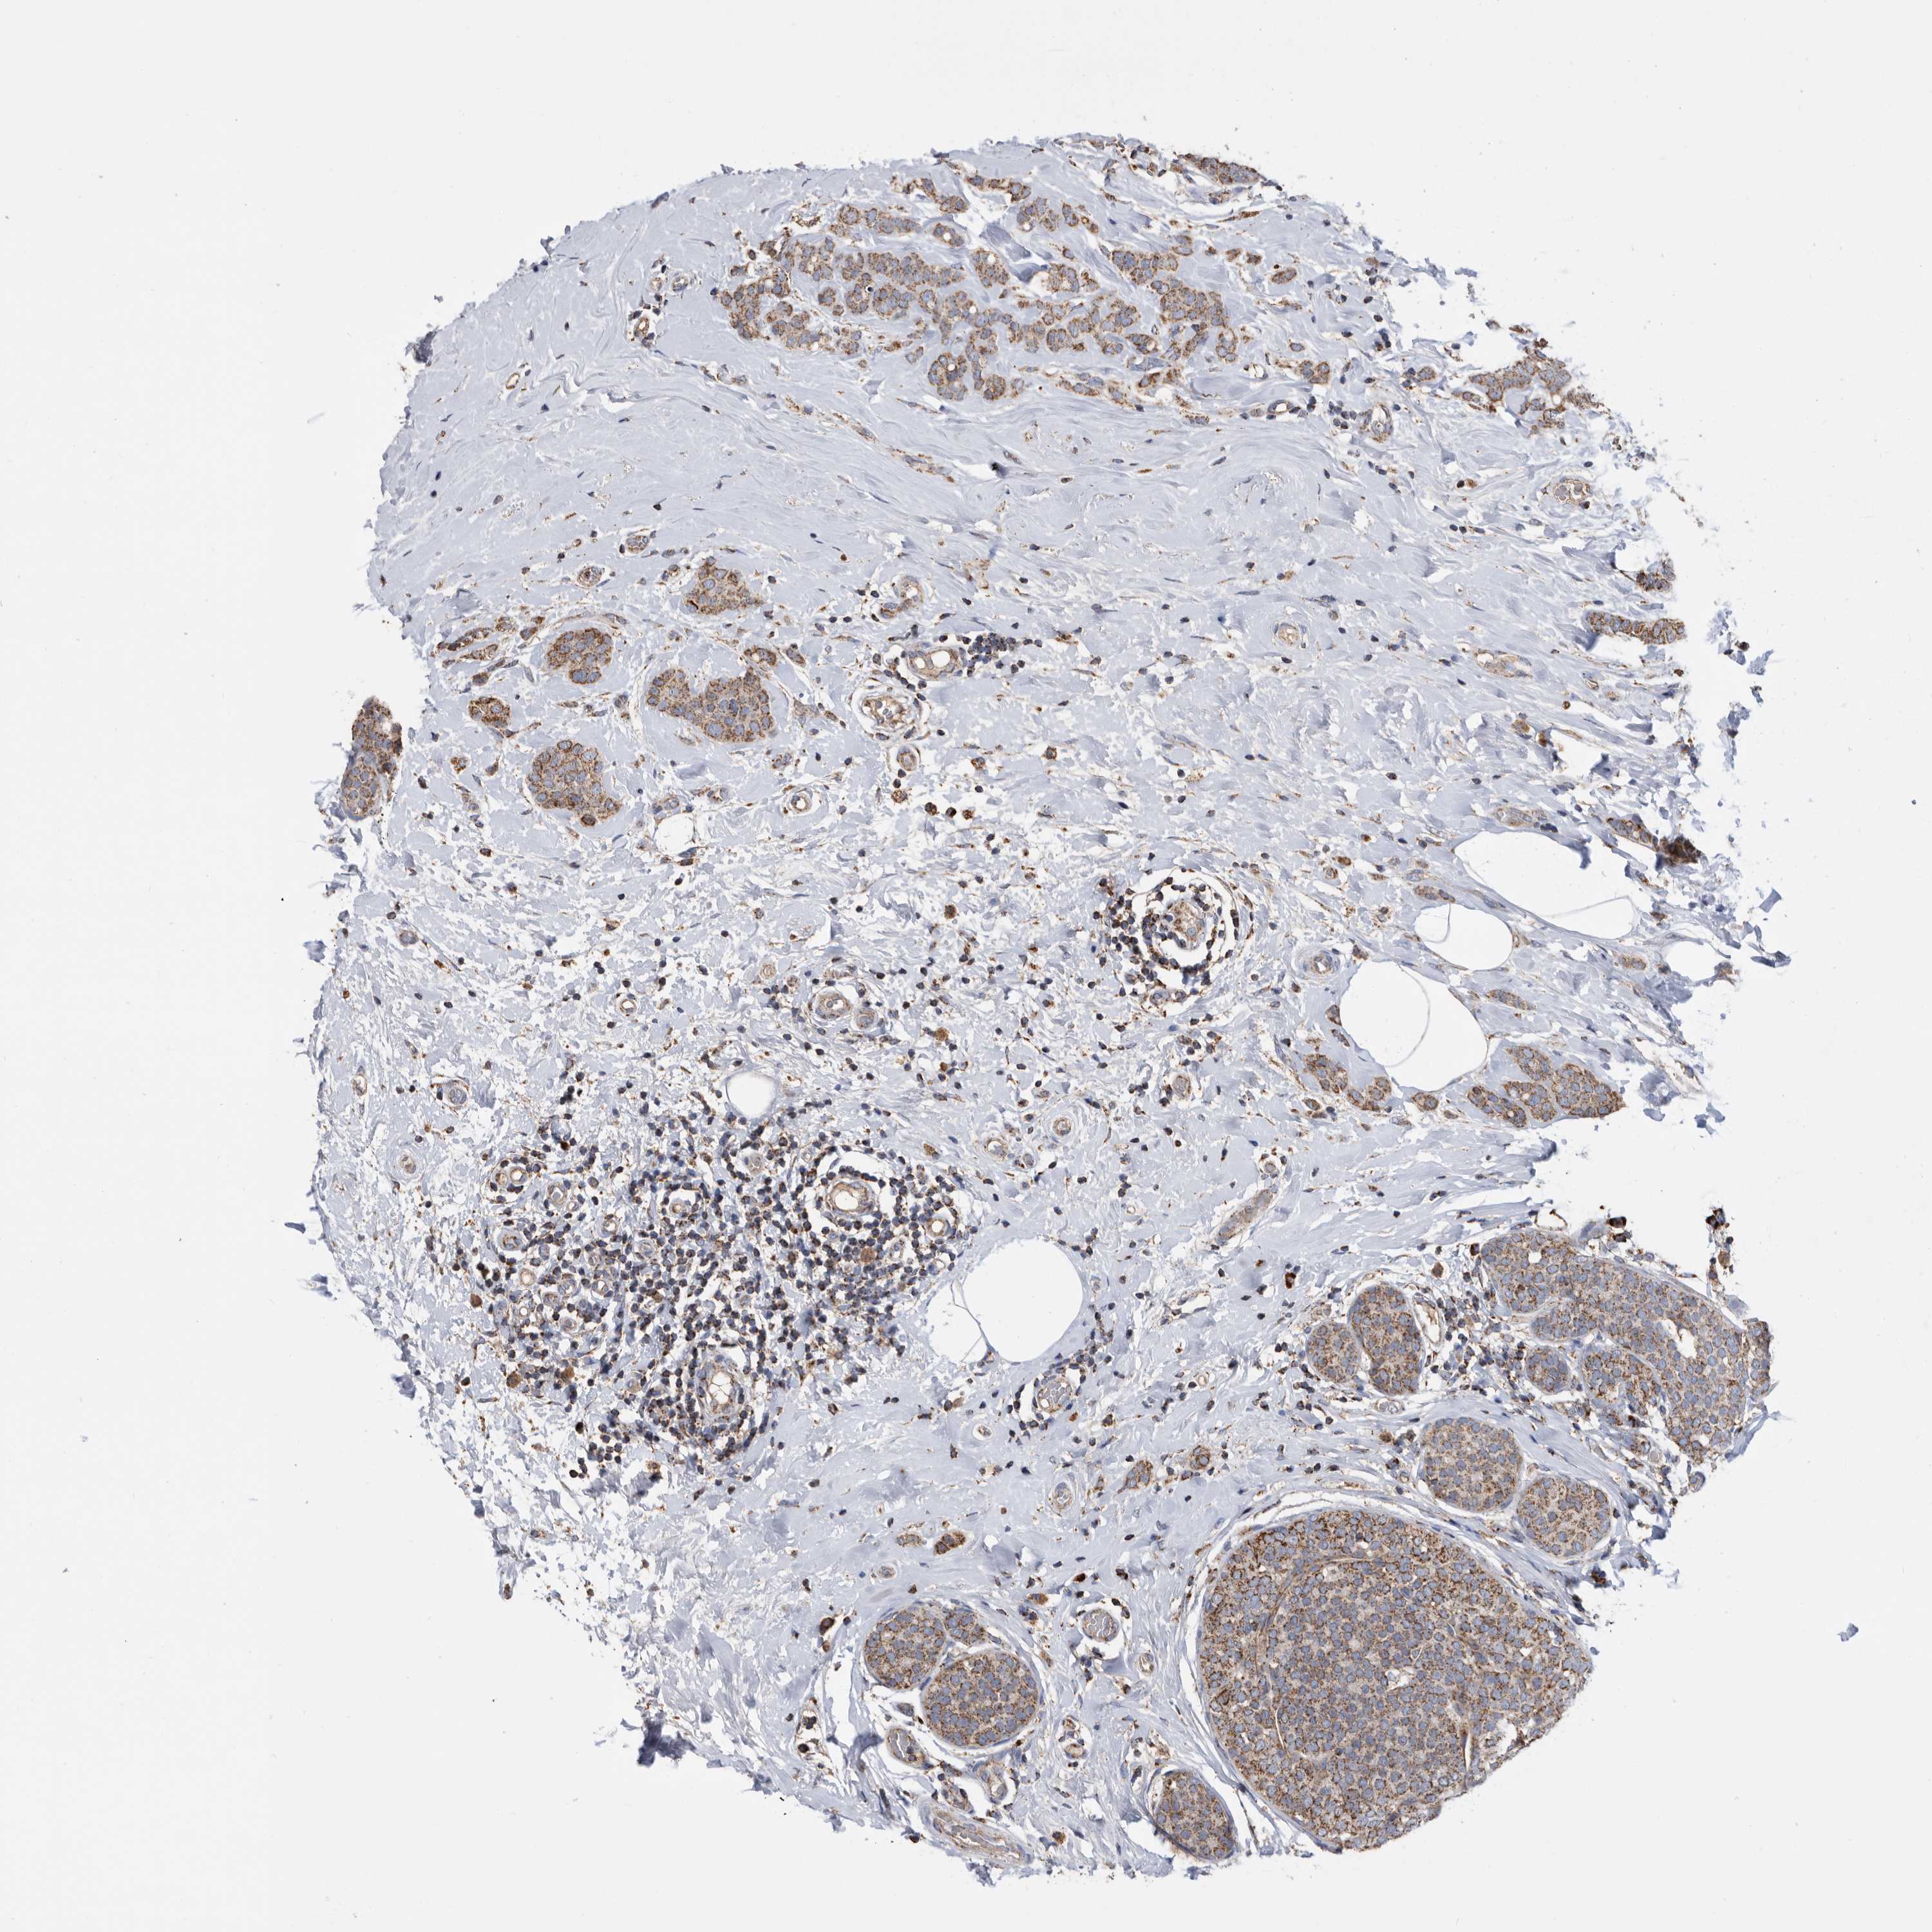

CANCER BREAST CANCER Show tissue menu

BRCA TCGA BRCA VALIDATION PROTEIN EXPRESSION